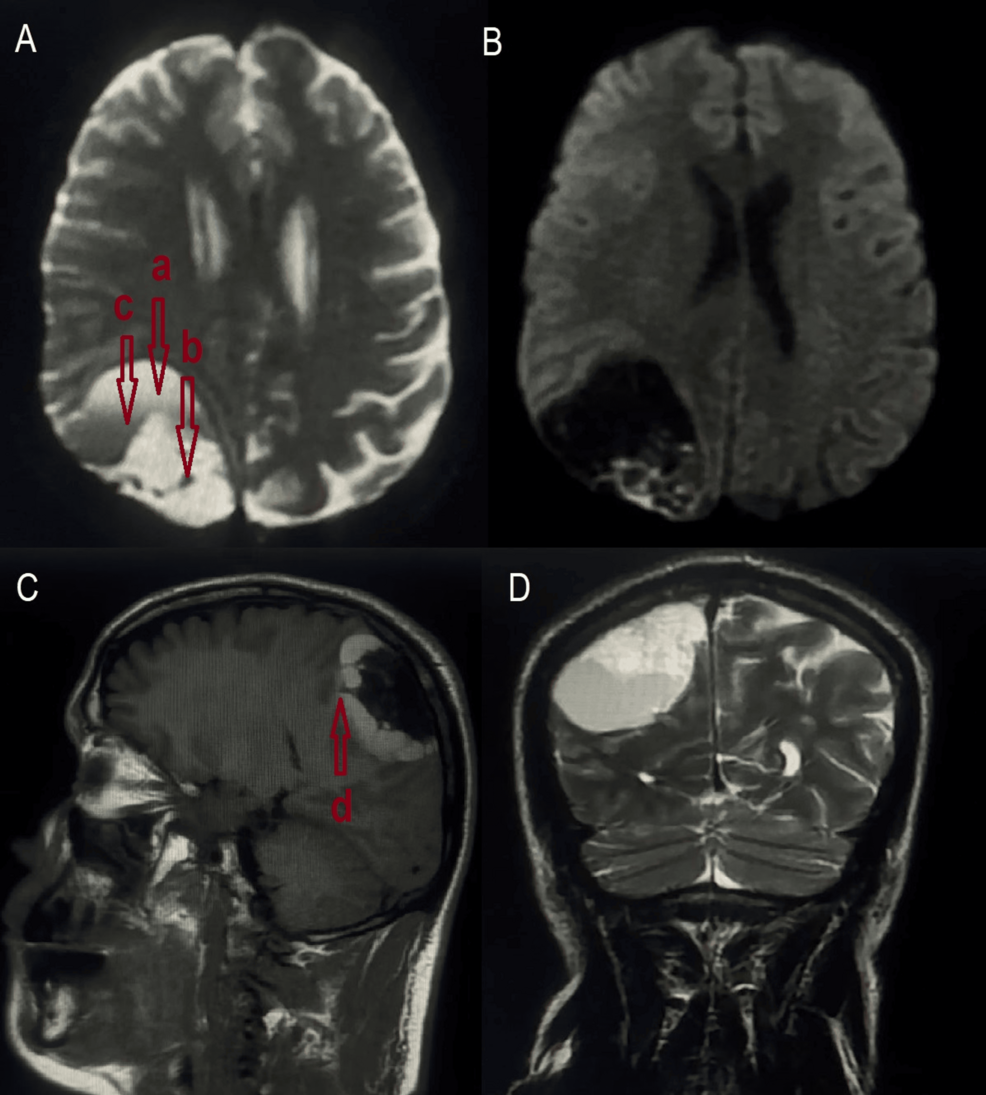

Cerebral Lymphangioma: A Clinical Case History | Cureus